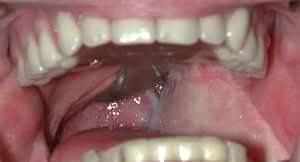

A pharyngeal speech aid prosthesis or speech bulb obturator is a removable device that treats velopharyngeal insufficiency by filling the pharyngeal space that cannot be closed through muscular function (37). A speech bulb obturator (Figure 2) usually has three parts: an anterior part (similar to a maxillary Hawley orthodontic retainer or removable dental prosthesis/complete denture), which can include prosthetic teeth in addition to obturation of the opening in the hard palate. The middle part of the device connects the anterior to the posterior part, while the posterior part is the bulb to correct or reduce the effects of velopharyngeal insufficiency. The bulb either goes upward behind the velum in the nasopharynx (if the remaining soft palate moves when the patients says “ah”) or the bulb can just be in contact laterally (if the remaining soft palate does not move). During velopharyngeal closure, the remaining soft tissue will move to contact the bulb resulting in the necessary closure. Ideally, when the velopharynx is not closed, there should be lateral space that will allow nasal breathing.

Traditionally, the functional contouring of a prosthesis utilizing functionally adapted impression materials such as modeling compound and mouth-temperature softening wax has been the foundation for prosthetic rehabilitation of soft palate abnormalities. When fabricating obturators for patients with these defects, instrumental visualization techniques can help avoid issues with under- or over-obturation. To assess velopharyngeal function, a fibreoptic nasal endoscope with a camera can be utilized. The flexible tip is positioned at an angle and rotated to ensure clear visibility of the velopharynx when at rest. The velopharyngeal valve is evaluated during breathing, speaking, and swallowing. For the assessment of velopharyngeal function during speech, phrases containing pressure-loaded consonants, such as “buy baby a bib” and “cherries and cheese”, as well as counts from 60 to 69, are used. These particular sounds are selected because they generate the most significant velopharyngeal movement. Afterward, the patient is instructed by a speech-language therapist on how to make the necessary adjustments to optimize speech production (34,38).